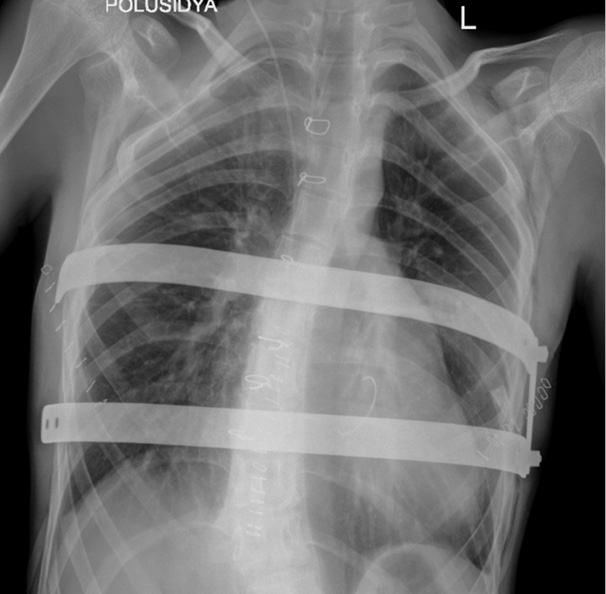

Плановое обследование включало обзорную рентгенографию грудной клетки в переднезадней проекции через сутки, а также на 5-й и 10-й день от момента операции, компьютерную томографию грудной клетки через трое суток после вмешательства. После проведения компьютерной томографии грудной клетки и вертикализации два дренажа удалены, правый плевральный дренаж удален на пятые сутки после дополнительного рентгенологического контроля (рис. 5, 6).

Рис. 5. Компьютерные томограммы до и после коррекции: a — исходный размер ретростернального пространства, до операции; б — контрольное исследование на 5-е сутки после операции.

Рис. 6. Компьютерные томограммы до и после коррекции: a — до операции; б — 5-е сутки после операции.